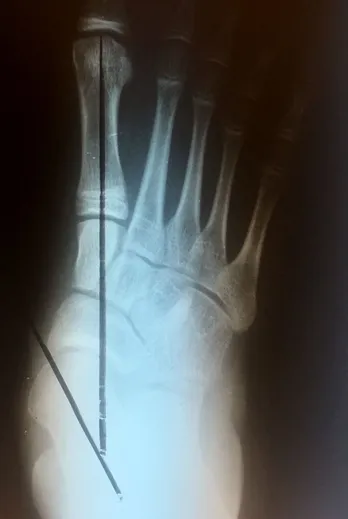

Xrays of Child above (pre and postop)

Pre-operative x-rays of the flatfoot with the talus deviated medially due to subluxing off the calcaneus causing the midtarsal joint to sublux laterally and uncovering of the talar head at the talo-navicular joint (left). The talus bone should line up with or be close to paralletl with a line drawn through the 1st metatarsal shaft (right). This is referred to as Meary's angle.

One case see an improvement in Meary's angle after surgical repair of the flatfoot with a subtalar joint implant which blocks the subluxation of the talus off of the calcaneus.